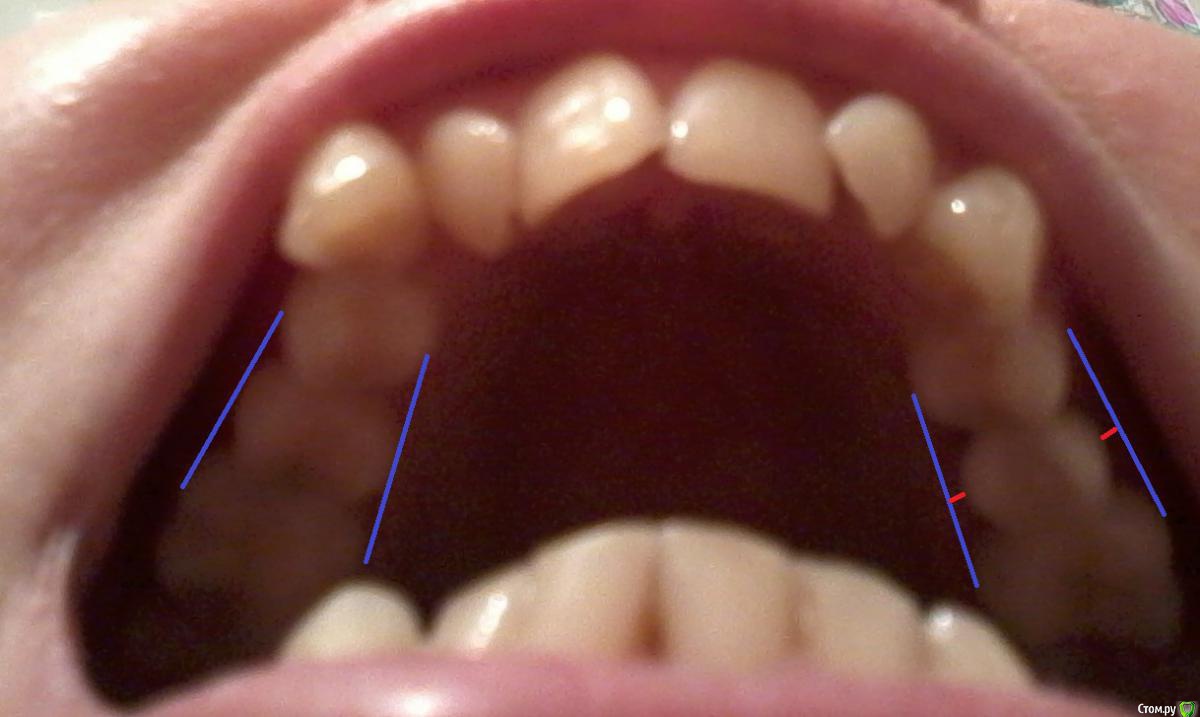

Natalia_ Опубликовано 23 сентября, 2015 Поделиться Опубликовано 23 сентября, 2015 Уважаемые специалисты, помогите советом. Имплант поставила в марте, верхняя 5, xive 3,8, пора протезировать, возникли проблемы (или не возникли, не знаю, или не проблемы), к которым не готова. Ортопед неожиданно сказала, что нижнюю 5-ку придется подпиливать, потому что она выпирает и коронка на верхнем импланте не поместится. (Непонятно, почему она мне 5 мес назад это не сказала, нижний зуб у меня не первый год так выпирает, и 5 мес назад все так и было) На вопрос, а сильно ли подпиливать и не допилим ли мы до дентина, глубокомысленно сказала, что тут она ничего не гарантирует. А чтобы этого избежать, можно нижнюю 5-ку задвинуть обратно, для этого нужна установка тяги, то есть поставить мини-имплант на нижнюю челюсть (не представляю куда его там вписать), к нему прикрепить какую-то фигнюшку, которая будет тянуть зуб на место. И записала меня сначала к ортодонту для консультации по поводу этого устройства, потом к ней (ортопеду) на слепок, потом к хирургу на установку этого мини-импланта. И тут я поняла, что протезироваться я кажется буду в другой клинике, потому что все как-то странно и непоследовательно, учитывая то, что каждую нашу встречу ортопед начинает с рассказа о брекетах и вреде неправильного прикуса для разных систем организма, несмотря на то, что мне 40 лет, и я вообще-то к ней со свежепоставленным имплантом пришла и хочу только один-единственный зуб, больше мне от нее ничего не надо. В другой клинике ортопед (приятный молодой человек) сказал, что предлагает мне индивидуальный абатмент, с винтовой фиксацией, то есть как я поняла, коронка крепится к этому инд абатменту и вся эта фигня закручивается в имплант. На вопрос видит ли какую-либо проблему, посмотрел еще раз на меня, на снимки и сказал, что не видит. Я обратила внимание на нижний зуб, и он сказал, что места да, немного, но можем вписаться с инд абатментом, может быть нижний ну не подпилить, а подшлифовать немного придется, в любом случае, сначала сделаем слепок, и тогда будет ясно. Это мне показалось логичным, про сначала слепок. В общем вопрос такой - может быть сразу понятно, хватит там места у меня или нет? И нет ли какой-н опасности в инд. абатментах (некачеств материал, могут треснуть или еще чего-н стоит опасаться)? И еще он сказал, что коронку эту на имплант надо ставить так, чтобы она стояла вплотную и немного давила на соседние зубы, - а не пострадают они от этого, стоит ли так втискивать? Ну и как вы считаете, нужна ли временная коронка, есль ли в ней какой-то смысл? В общем, много вопросов, и главный - продолжать ли мне поиски ортопеда... Помогите, пожалуйста, советом, как-то сложно все вдруг оказалось. Ссылка на комментарий

Natalia_ Опубликовано 14 октября, 2015 Автор Поделиться Опубликовано 14 октября, 2015 Готово, посмотрите, пожалуйста, что получилось.В принципе думаю смогу привыкнуть. Смущают тонкие острые края (ну, не режут конечно, но свои потолще и покруглее зубы, у нового краешки прямо истонченные по сравнению с ними и внутри такой закругленный), и хотелось бы его чуть-чуть повыпуклее его что ли снаружи. Как считаете, это уже придирки?(Я понимаю, клыки внимание привлекают, но мы сейчас не о них.)Вообще готова с ним жить. Наверное. Не слишком его истончили? Ссылка на комментарий

Natalia_ Опубликовано 14 октября, 2015 Автор Поделиться Опубликовано 14 октября, 2015 Поняла что меня смущает. Маловат сделали, да? Переделывать? Ссылка на комментарий

Чертков Александр Опубликовано 22 октября, 2015 Поделиться Опубликовано 22 октября, 2015 По данным фото все неплохо. Ссылка на комментарий